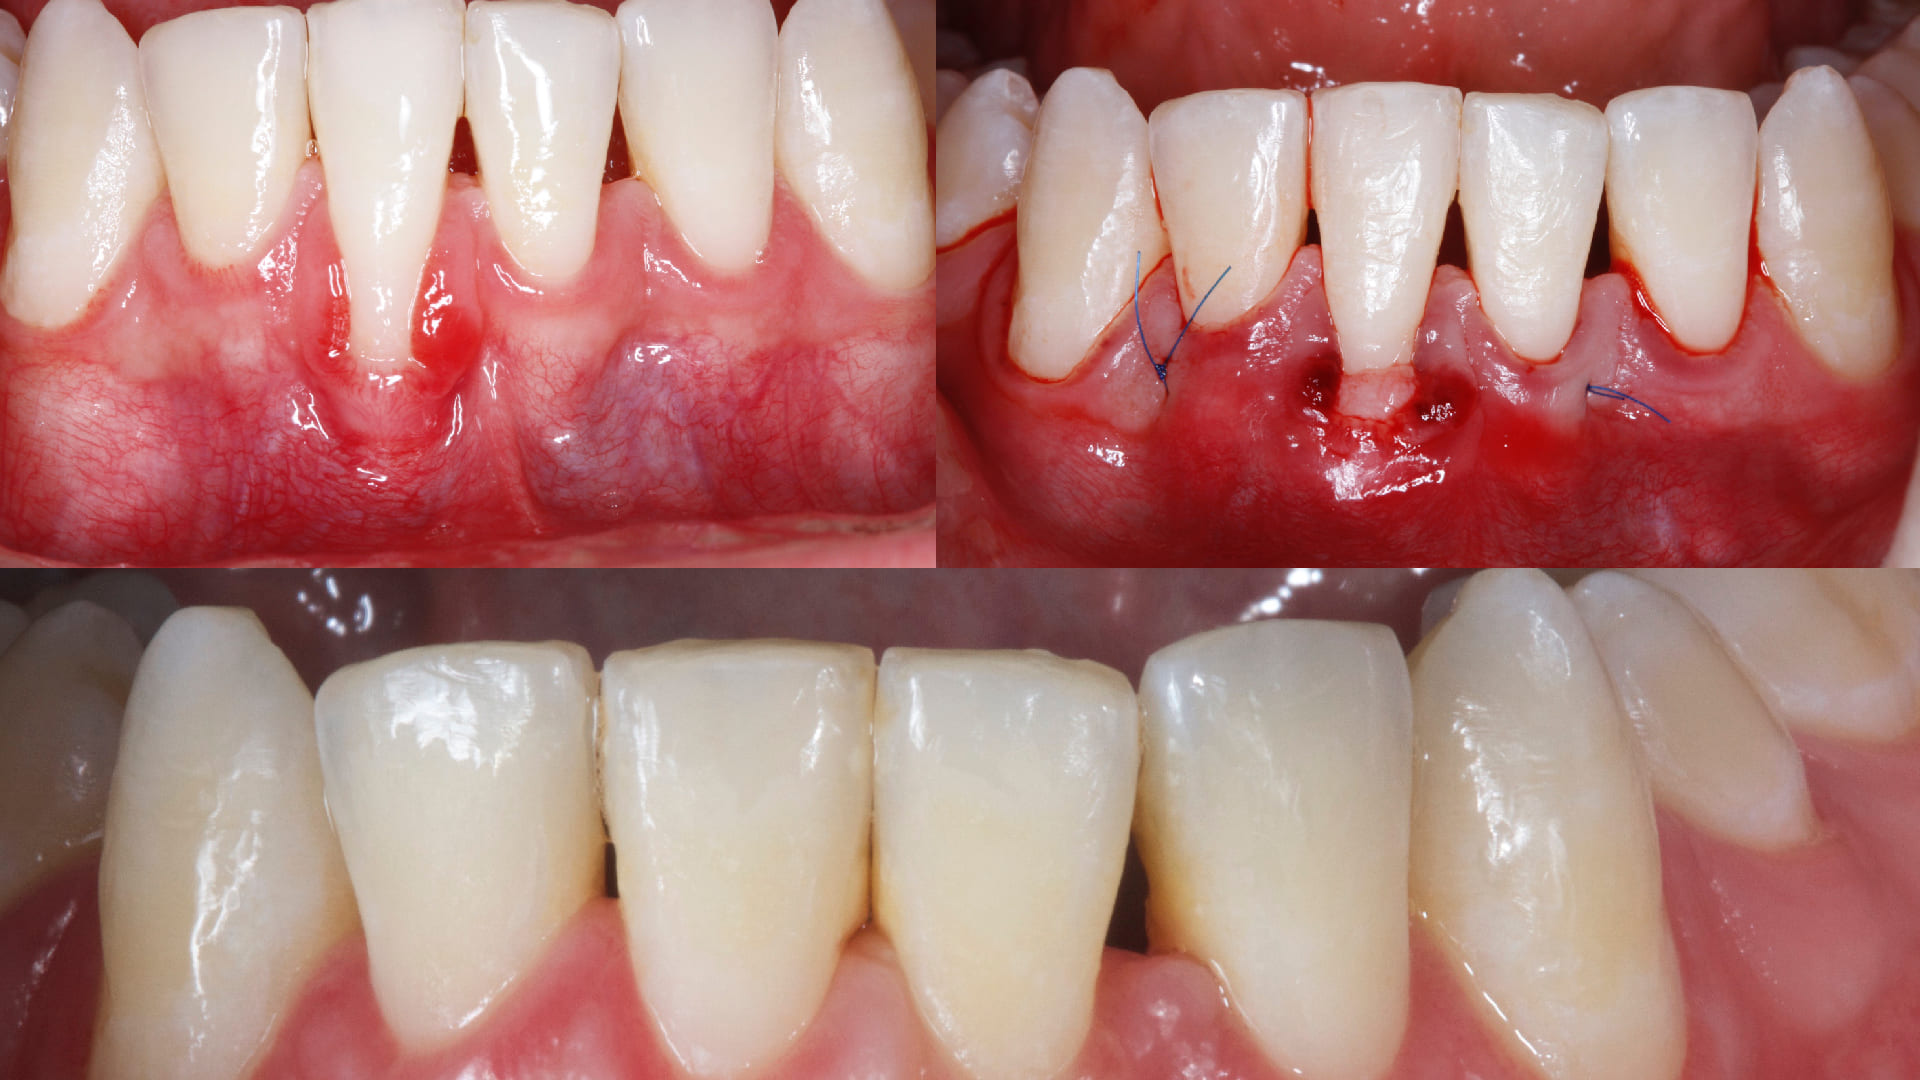

Root Coverage procedures.

CLINICAL CASES